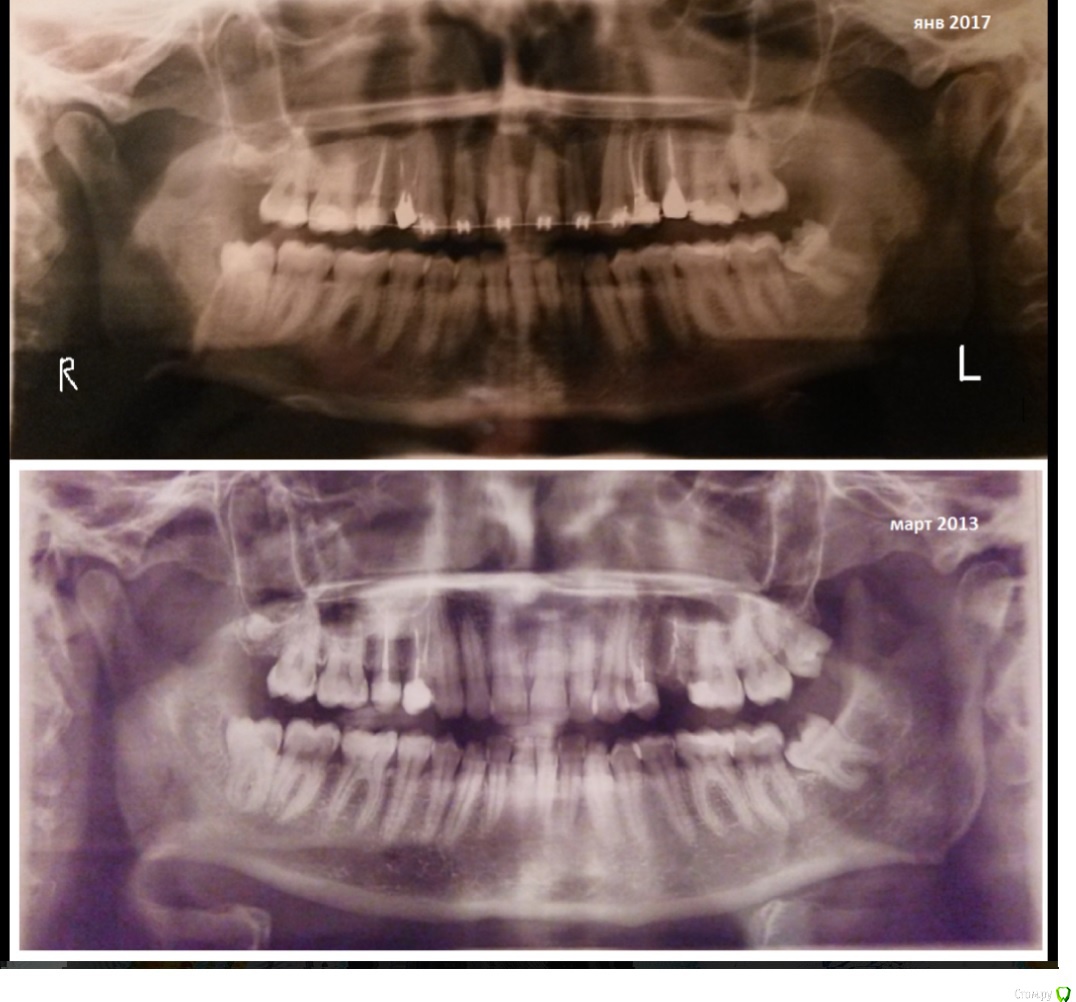

Здравствуйте! Мне 34 года, ношу брекеты 10 мес. на ВЧ (месяц как перешли на дугу 17/22), ориентировочный срок выравнивания (заявленный ортодонтом) – 1-1,5 года. Лечение без удаления, но на 2 корнях установлены штифты под коронки (на «4» справа и «5» слева).

О лечении: старт был со слепка (мне его не выдавали)  и ОПГ 3-летней давности. Асимметрию не обсуждали. По моей инициативе ставили только на 1 челюсть, причина – совокупность факторов (основной - это озвученный срок лечения:  на 2 челюсти – не менее 3-5 лет…в моём возрасте ( 33 года на тот момент) мне это показалось неоправданным). О том, что это может затянуть лечение, наслышана..

2)     Вторая проблема – зубы быстро/легко/постоянно перемещаются с правой стороны, но слева за последние 8  мес. (из 10 мес.), при наличии небольшого «зазора» между 3 и 4, практически не двигаются. На  срок лечения в 1-1,5 года уже смотрю скептически. Сделала новую ОПГ –  врач сказал, что всё отлично, просто нужно ждать.